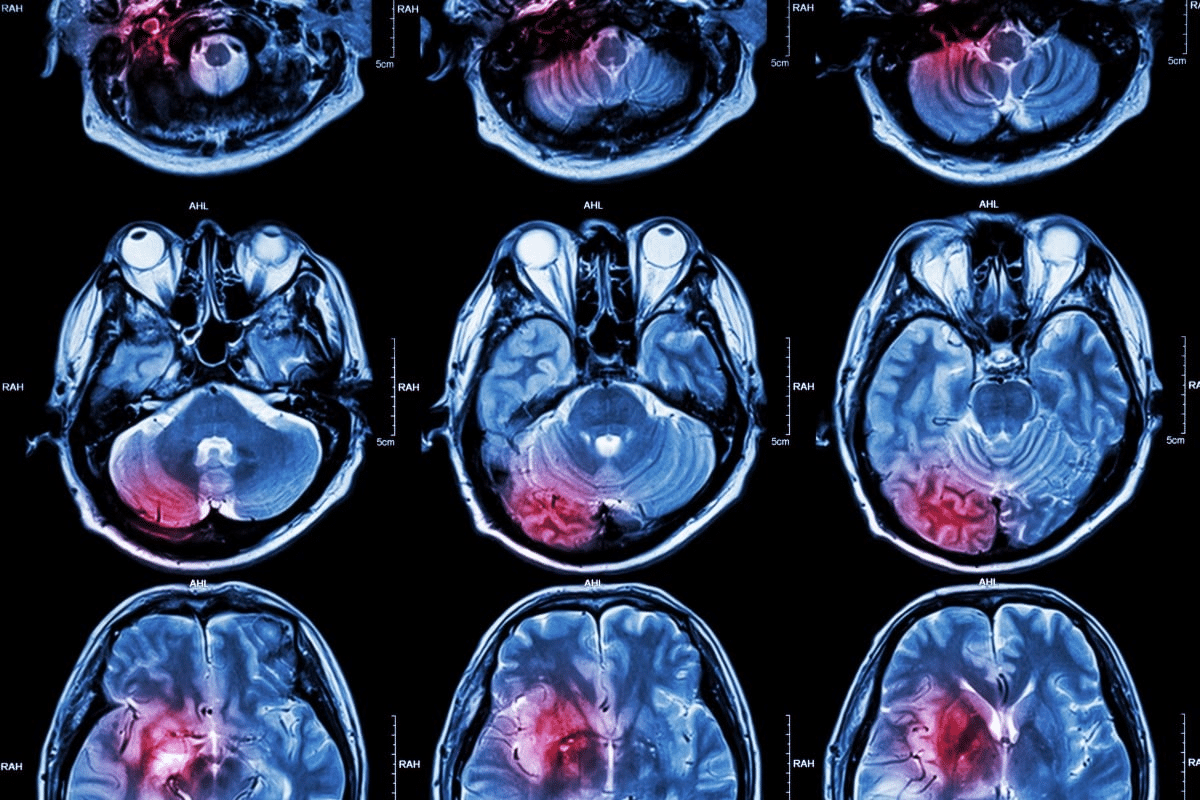

Brain Imaging Techniques

Imaging shows us brain injuries. We use MRI and CT scans to see brain damage. This helps us understand the damage.